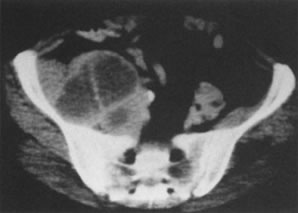

A 61-year-old woman with endometrial cancer. Note enlargement of the uterus (u) with a central area of hypodensity and the surrounding ascites (a).